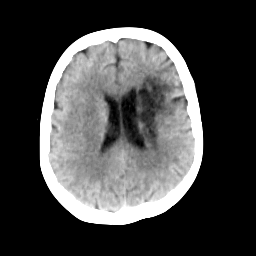

In this paper, we propose a bidirectional learning model, known as dual contrast cycleGAN (DC-cycleGAN), for medical image synthesis from unpaired data. Specifically, a dual contrast (DC) loss is formulated that leverages the advantage of samples from the source domain as negative samples to indirectly build constraints between real source and synthetic images via discriminators, and synthesize images more related to the target domain by enforcing the synthetic images to fall far away from the source domain. In addition, structural similarity index (SSIM) [35] and cross-entropy (CE) [48] are integrated into the DC-cycleGAN structure to avoid disappearing gradient information that is caused by a mean absolute error (MAE) and synthesizing irrelevant images. SSIM considers luminance [35] and CE converges fast as its back-propagation error is less than MSE [28]. As can be seen in Figs. 1 and 2, using SSIM and CE with dual contrast can generate more clear and accurate MR images as compared with that of MAE and MSE, and SSIM and CE without dual contrast loss. Although both SSIM and CE with dual contrast and without dual contrast generate similar CT images, SSIM and CE with dual contrast quantitatively generate better images as shown in Table 4. The experimental results indicate that DC-cycleGAN is able to consider more complex features such as structure in synthesizing images and produce remarkable results as compared with other state-of-the-art methods reported in the literature.

Tables 3 and 4 show the results of MR and CT synthesis, respectively. As can be seen, all components play vital role in both tables. SSIM & CE (w) performs significantly better than other losses in synthesizing MR images. This also can be seen visually in Fig. 1. In contrast, SSIM&CE (w) performs slightly better than SSIM&CE (wo) in synthesizing CT images, both generate more or less similar CT images (see Table 4).